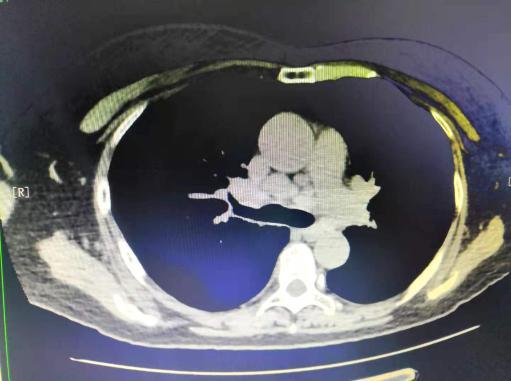

病例1:结核所致右主支气管瘢痕性狭窄

病例2 恶性肿瘤所致气管狭窄

理结果:鳞癌.